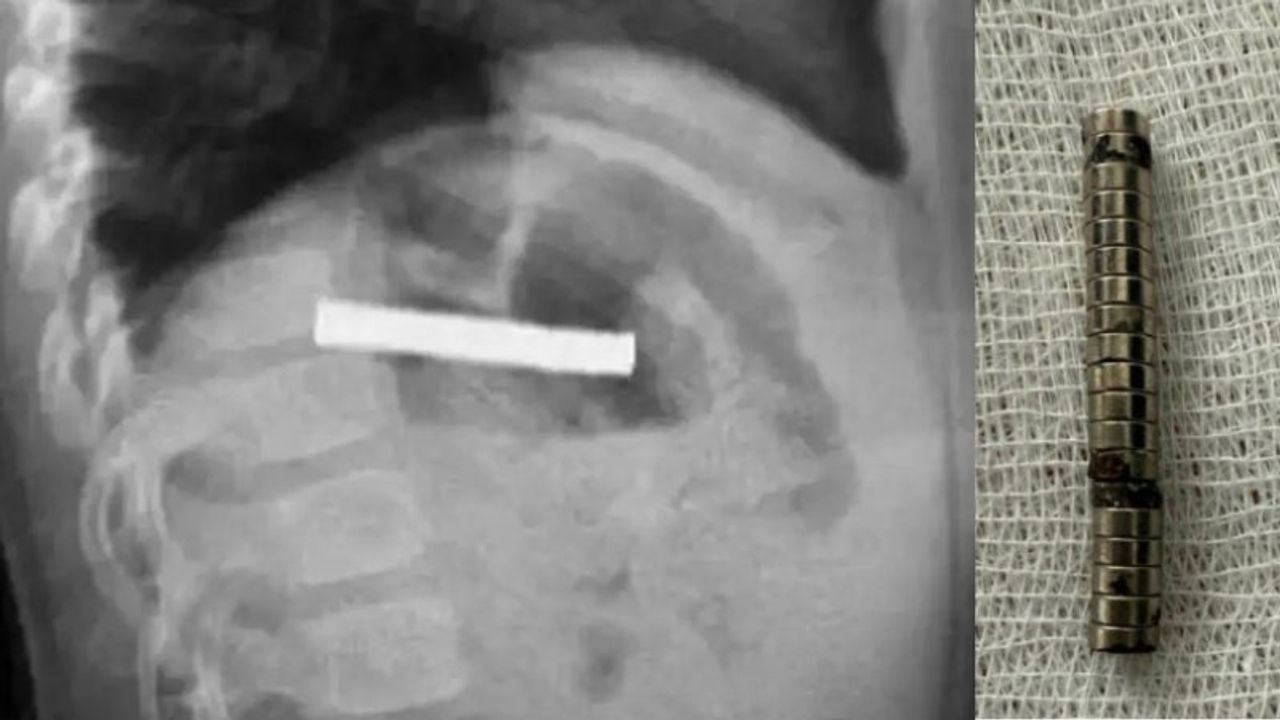

Erzurum’da 3 yaşındaki bir çocuğun rahatsızlanması sonrası ailesi hastaneye başvurdu. Yapılan muayene sonrası çocuk Elazığ’a sevk edildi. Fırat Üniversitesi Çocuk Gastroenteroloji Hepatoloji ve Beslenme Bilim Dalı Başkanı Prof. Dr. Yaşar Doğan, endoskopik yöntemle çocuğun yemek borusuna yapışmış 19 adet mıknatısı başarılı bir operasyonla çıkardı.

Mıknatıslar uzun süre yemek borusunda takılı kalmasından dolayı zedelenmeler olurken, çocuğun sağlık durumunun ise iyi olduğu ve taburcu edildiği öğrenildi.